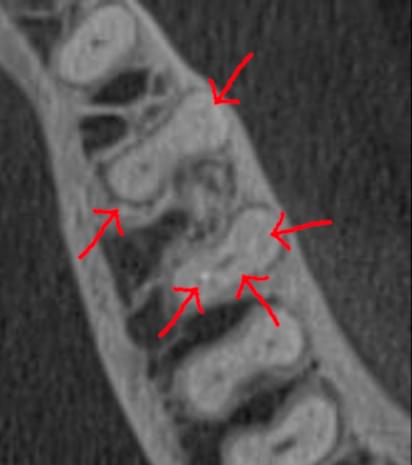

Зуб — це не просто монолітний об'єкт, а складна система мікроканалів. На плоскому 2D-знімку вони часто перекривають один одного, створюючи ілюзію простої анатомії.

Непомічений канал — це джерело майбутньої інфекції та причина «загадкового» болю після лікування. Завдяки високій роздільній здатності обладнання MyRay, лікар бачить кожен мікронний канал ще до того, як візьме до рук інструмент.